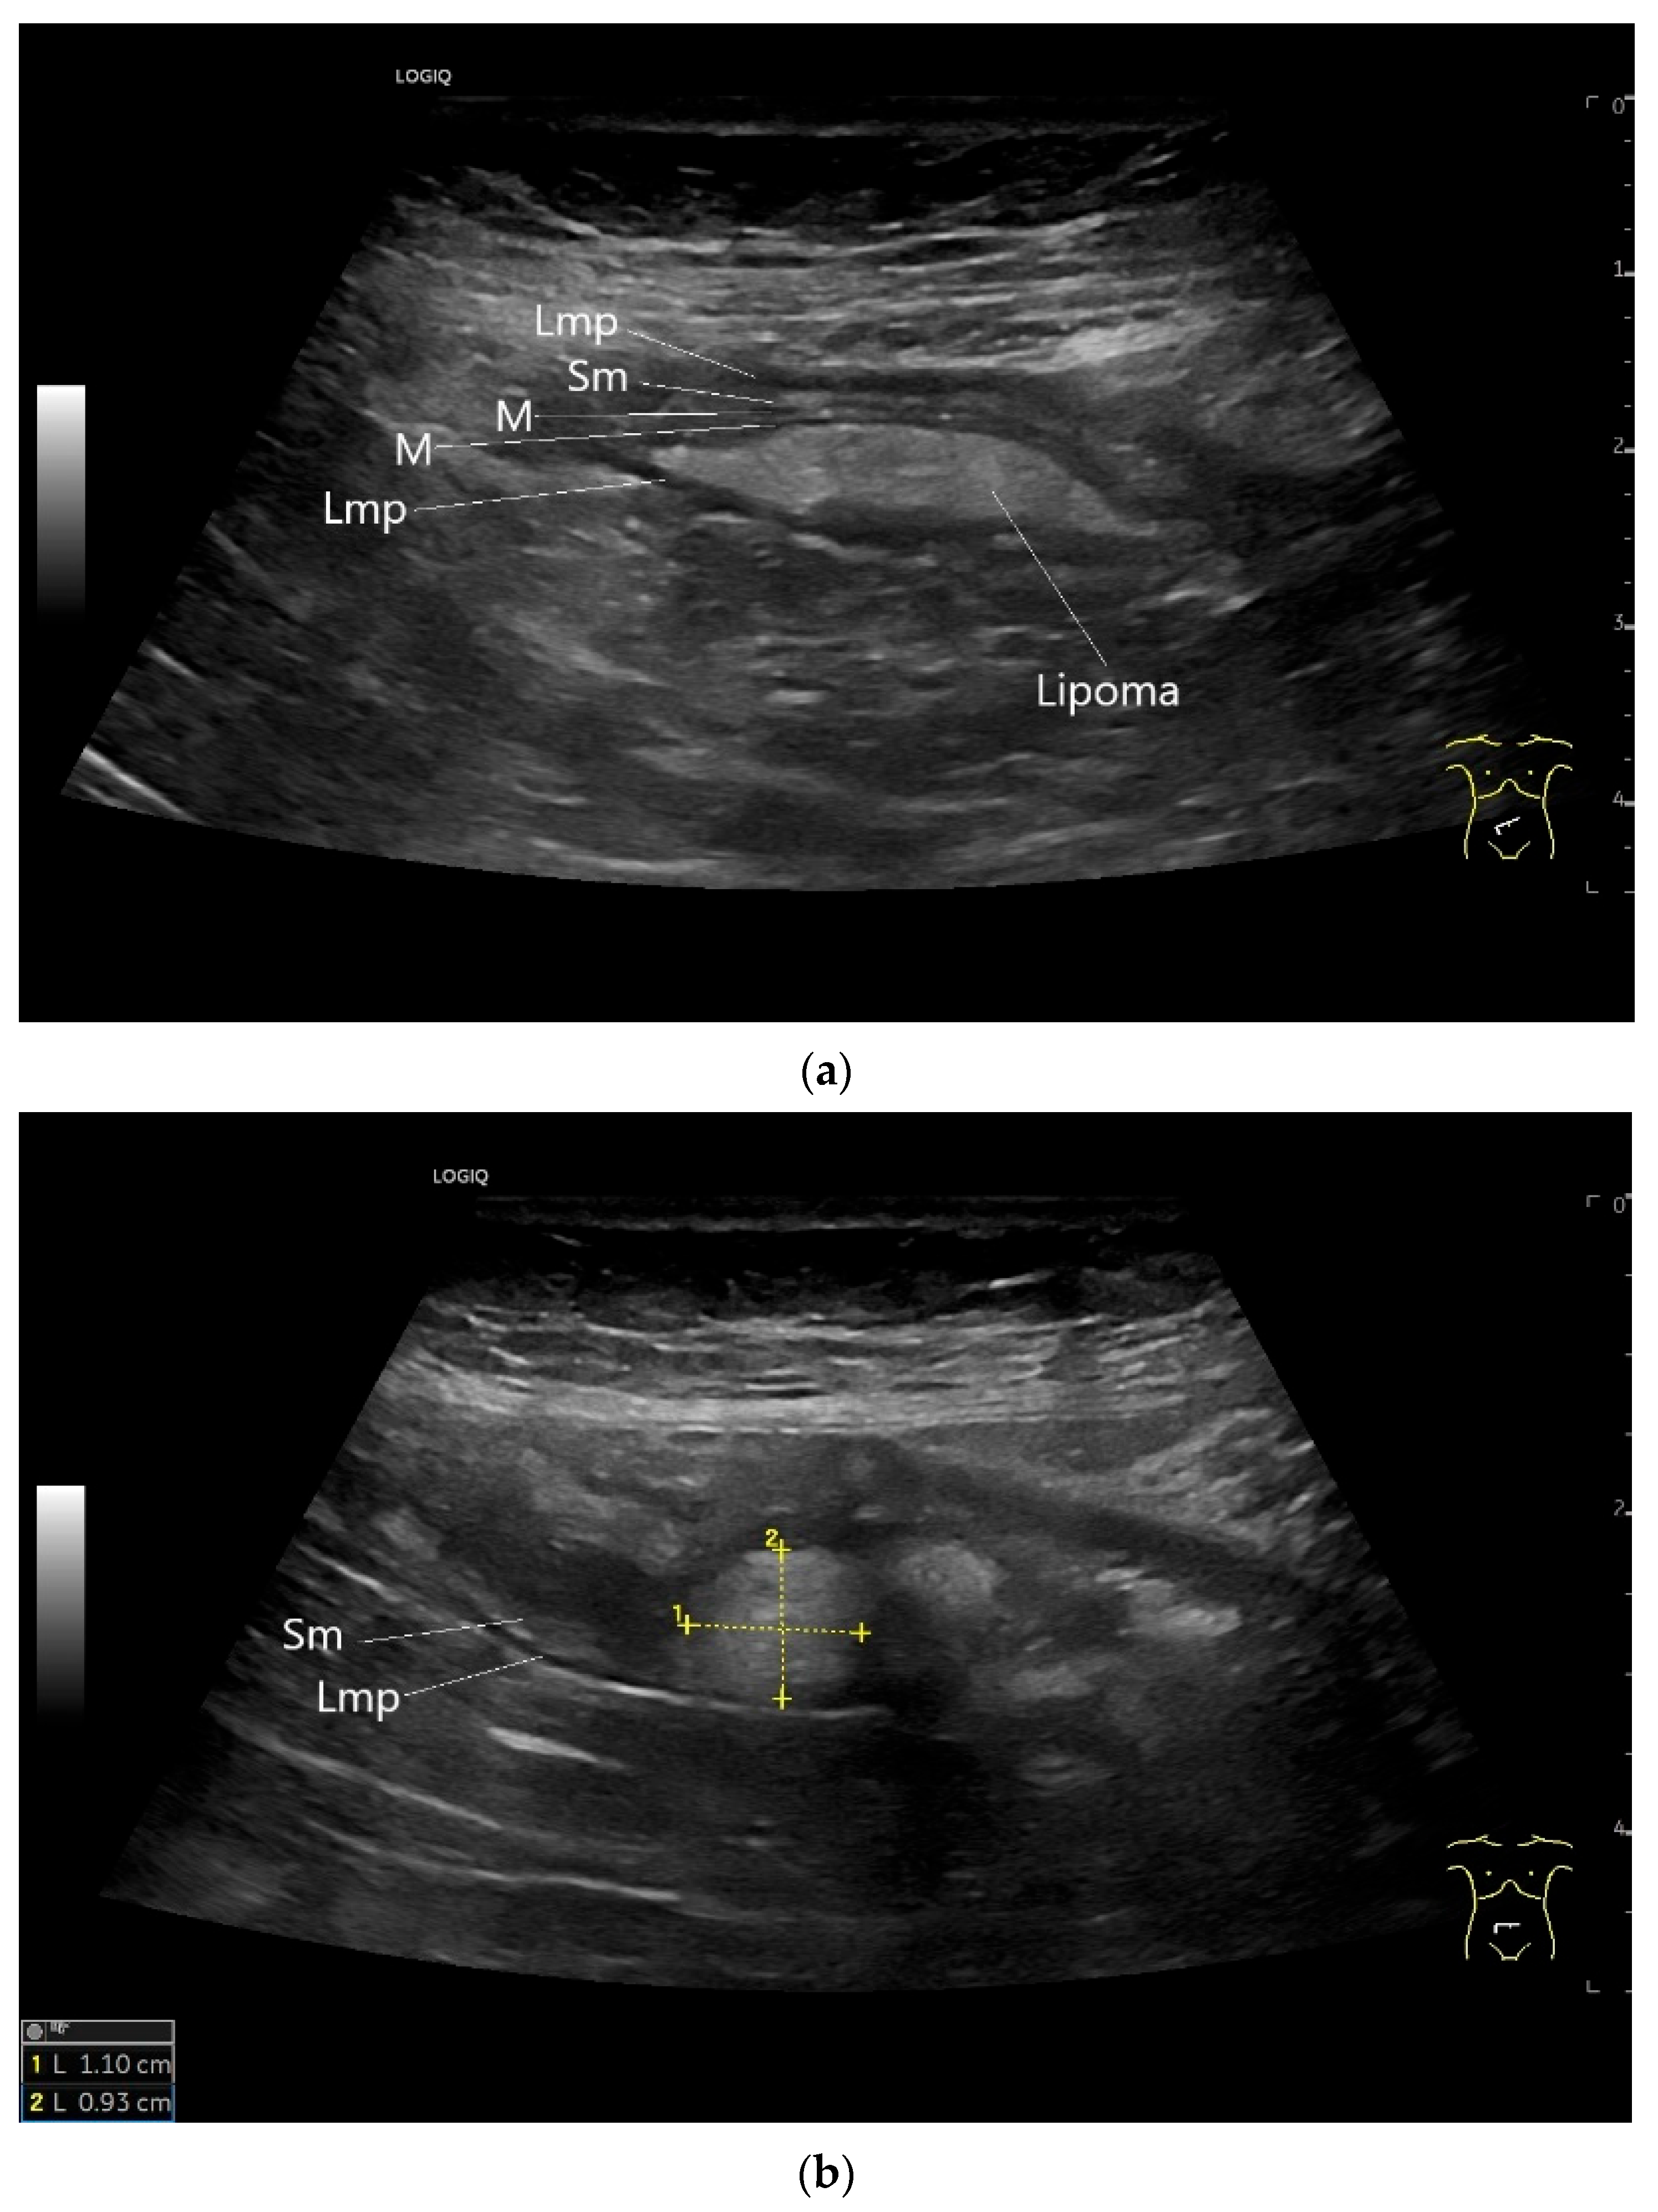

| Lipoma | Found in any part of the gastrointestinal tract. Rare in the small intestine and there predominantly located in the ileum. | Smoothly bordered oval/round lipomatous lesions, usually originating in the submucosa. Yellowish shimmering impressions on endoscopy, soft on contact. |

| Lymphangioma | Anechoic cystic lesions related to the small intestine wall. No vessels on CDI, Nonenhancement on CEUS. They move with the small intestine. |